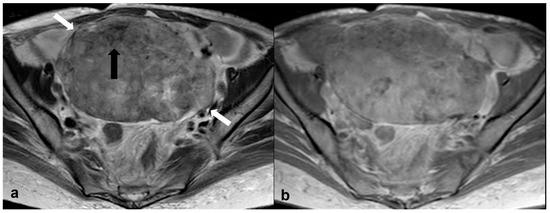

2.3.4. Lymphoma

2.3.5. Metastases